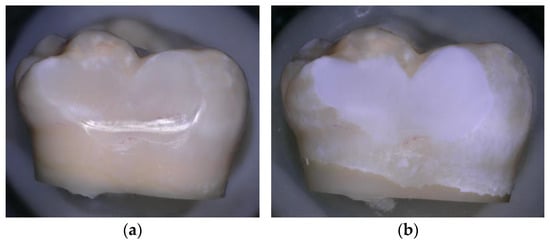

In order to induce artificial caries-like lesions on enamel for the demineralised enamel group, the following pH-cycling protocol was used: initial lesions were prepared on 21 enamel samples, immersed into 20 mL of demineralising solution, and contained in a small plastic bottle. The bottles were maintained at 25 °C in a constant-temperature incubator, without agitation. The demineralising solution was prepared from reagent grade chemicals and nominally contained 100 mmol/L lactic acid, 18.0 mmol/L calcium chloride, 7.8 mmol/L monobasic potassium phosphate, and 3 mmol/L sodium azide as a bacteriostat. The pH was adjusted to a pH of 4.3 with potassium hydroxide. In this fashion, subsurface enamel lesions were produced over a 2-week period, with the demineralising solution changed weekly. [27,28] (Figure 1).

Figure 1.

(a) Sound enamel before demineralisation; (b) Enamel after demineralisation, photographed using a confocal tandem scanning microscope (Keyence 5000 VHX digital microscope Belgium) with a 50× air objective in reflection scanning mode.